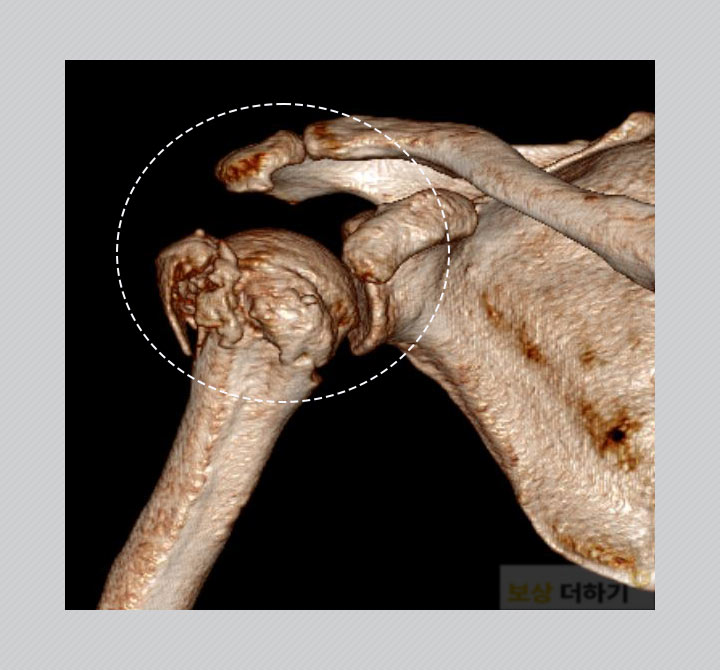

서 00 님은 렌터카 사무실의 관리 소홀로 미끄러운 바닥에 넘어져 다치셨습니다. 팔이 펴진 상태로 충격을 받으면서 큰 부상으로 이어지게 되었습니다. 우측 견관절부 근위 상완골 골절 S42290 오른쪽 위팔뼈인 상완골, 그중에서도 어깨 쪽(근위부)이 골절된 것입니다.

상완골 근위부는 어깨 관절과 인접하여 팔의 움직임에 직접적인 영향을 미칠 수 있습니다. 따라서 골유합이 잘 이루어져 어깨 관절 운동의 제한과 같은 후유 증상이 남지 않도록 수술 치료를 받으셨어요.

다음과 같이 뼈가 잘 붙을 수 있는 위치로 정복을 한 후 고정을 해주는 수술을 시행 받았습니다. 수술 후에는 정기적으로 내원하여 유합이 잘 되는지 확인을 받으셨고, 물리치료와 재활운동을 병행하며 어깨 관절의 운동 범위 회복을 위해 노력하셨습니다. ▽ 관혈적 정복술 및 내 고정술